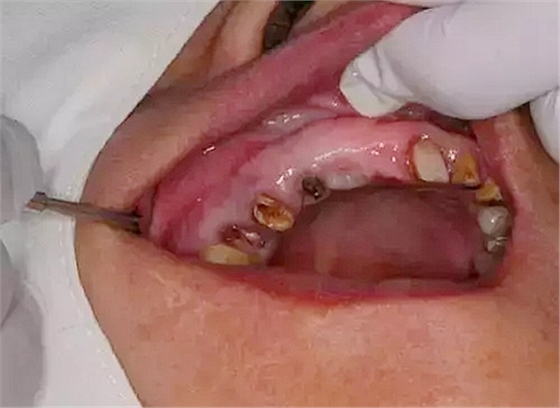

處理:14、15微創(chuàng)拔牙+拔牙位點(diǎn)保存術(shù)。

?患者口腔內(nèi)部情況